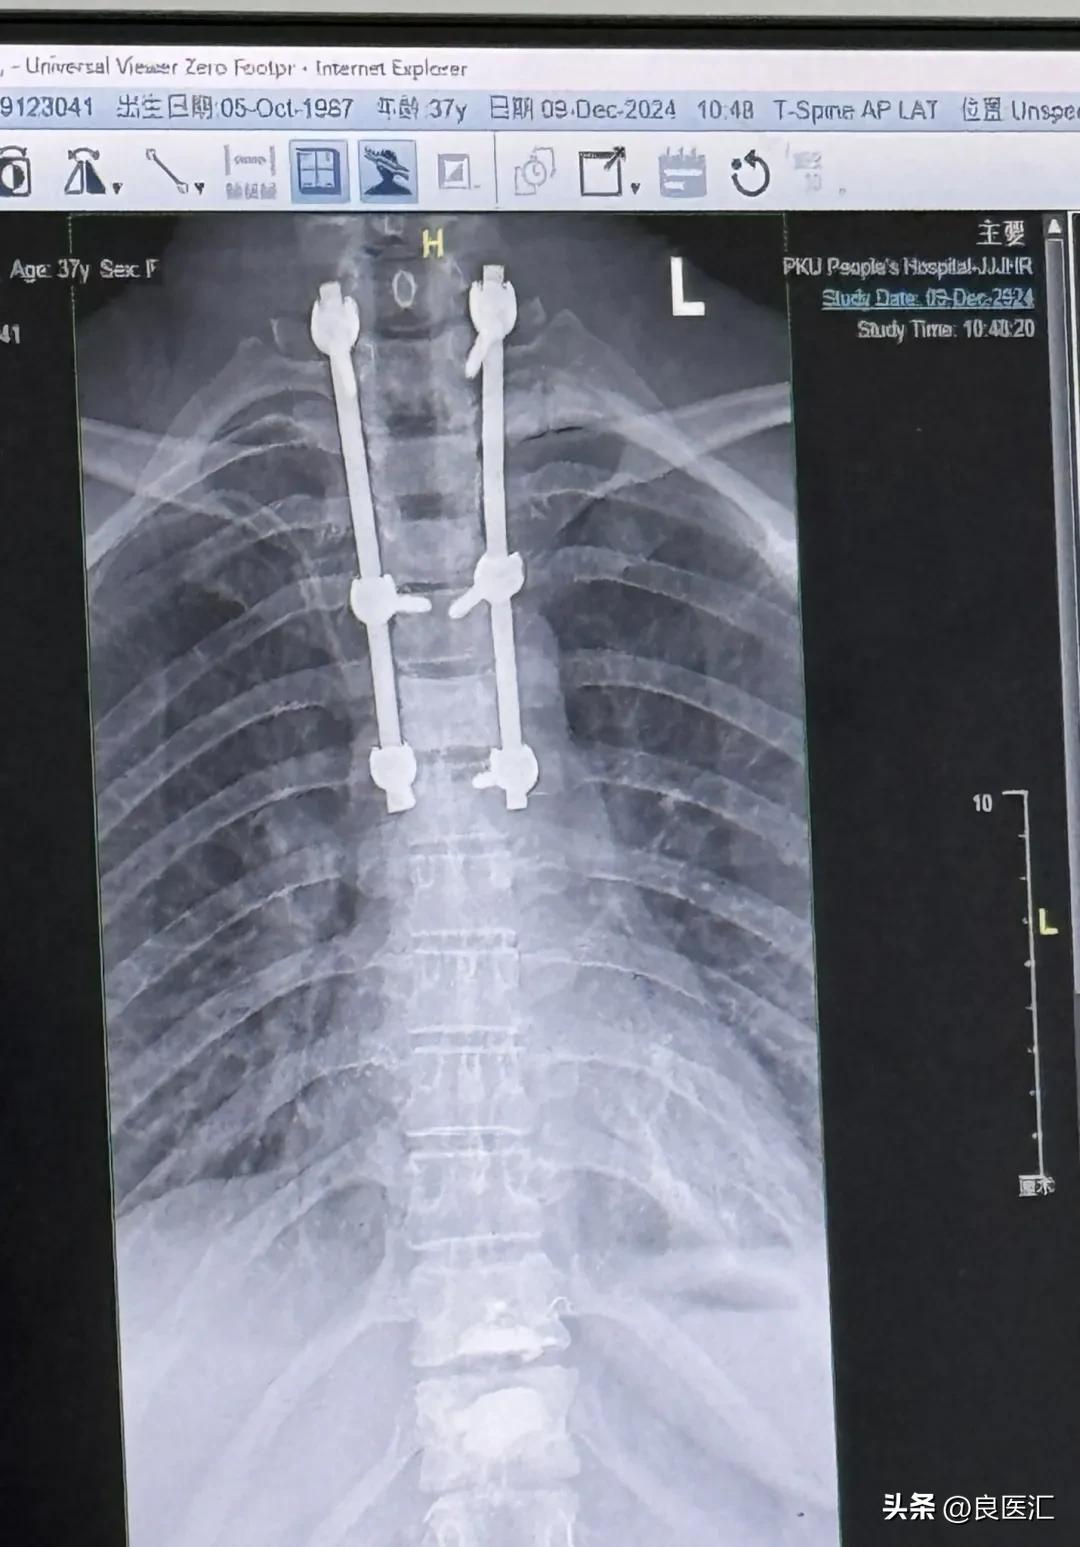

壳壳脊椎X光片(脊髓减压术后,双钛合金支架和钢钉永远留在身体里)

当新加坡医生拒绝壳壳入组临床试验时,壳壳正因突发脊髓压迫坐在轮椅上难以起身行走。仅仅48小时前,她满怀希望飞抵狮城,期待着加入一个针对罕见肺癌靶点ROS1融合的临床试验,那是她耐药后的新希望。然而,命运在抵达的周末给了她沉重一击——突发严重的脊髓压迫。当时,医生和家属都认为壳壳的身体状况难以承受长途飞行的压力,需考虑留在新加坡进行治疗,手术费、护理费及家属陪护费用合计,预计在50-80万元人民币。壳壳思考再三做出了决定:“回国治疗!”周二深夜出发,周三直奔医院,周四第一个被推上手术台——一场及时的椎管减压术,将她从瘫痪边缘拉回,自费部分仅8000余元,与新加坡的天价预估相差千倍。